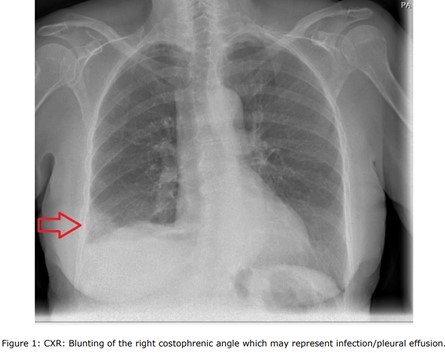

A chest x-ray was obtained, revealing right sided blunting costophrenic angle which may represent infection/pleural effusion (Figure 1). The electrocardiogram (ECG) showed a normal sinus rhythm (Figure 2). Blood tests, including C-reactive protein (CRP) which is 187 mg/L 0 - 5 and white blood cell count (WBC): 16.3 109/L 4.0 - 10.0, despite having oral amoxicillin 500 mg QDS by the GP for 7 days. Troponin T <13 ng/L. Urea and Electrolytes were normal. The Dimmer test result was 2210 ng/m, indicating high levels. Additionally, a COVID-19 test was conducted, which yielded negative results. Blood cultures and sputum gram stain with culture were negative, as were urinary antigen tests for Streptococcus pneumoniae and Legionella. N-terminal pro B-type natriuretic peptide (NT-pro BNP) and Echocardiogram was normal left ventricular (LV) function and no wall motion abnormalities with normal right ventricular (RV) function size.

Figure 1: CXR: Blunting of the right costophrenic angle which may represent infection/pleural effusion.